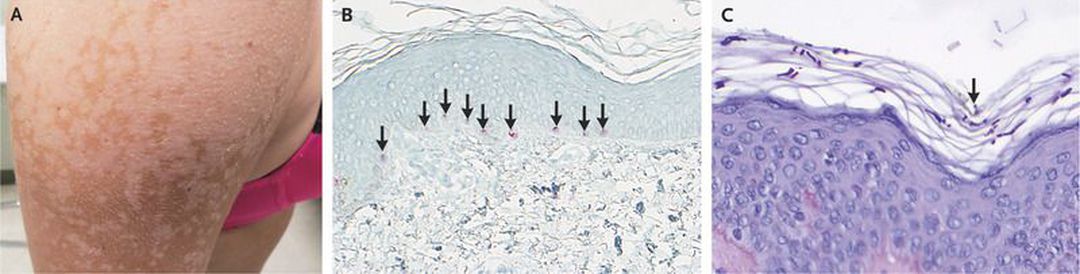

A 24-year-old woman presented with a 12-year history of a depigmenting rash. The rash was most notable in the summer months, with remission during cooler seasons. She reported prominent scaling of her skin, particularly after showering. Over the preceding 2 to 3 years, the rash had spread to include her entire torso with extension down her arms. She was concerned that facial involvement might occur. Previous therapies with multiple topical antifungal agents had not regenerated skin pigmentation. Physical examination revealed large, coalescing, hypopigmented patches and macules on her torso and upper arms (Panel A) with scant scaling. A skin biopsy was performed to evaluate for vitiligo. Melan-A staining confirmed a normal presence of melanocytes (Panel B, arrows). Subsequent periodic acid–Schiff staining revealed the presence of yeast in a “spaghetti and meatball” pattern in the superficial epidermis (Panel C, arrow). A diagnosis of tinea versicolor was made. Scaling that results from stretching or scraping of the skin is suggestive of tinea versicolor and should prompt examination under the microscope, when possible, of skin scrapings treated with potassium hydroxide or chlorazol black E. Given the extensive skin involvement, the patient was treated with a course of oral fluconazole and topical ketoconazole; the patient was lost to follow-up. The process of skin repigmentation may take months once the fungal cause is eliminated.